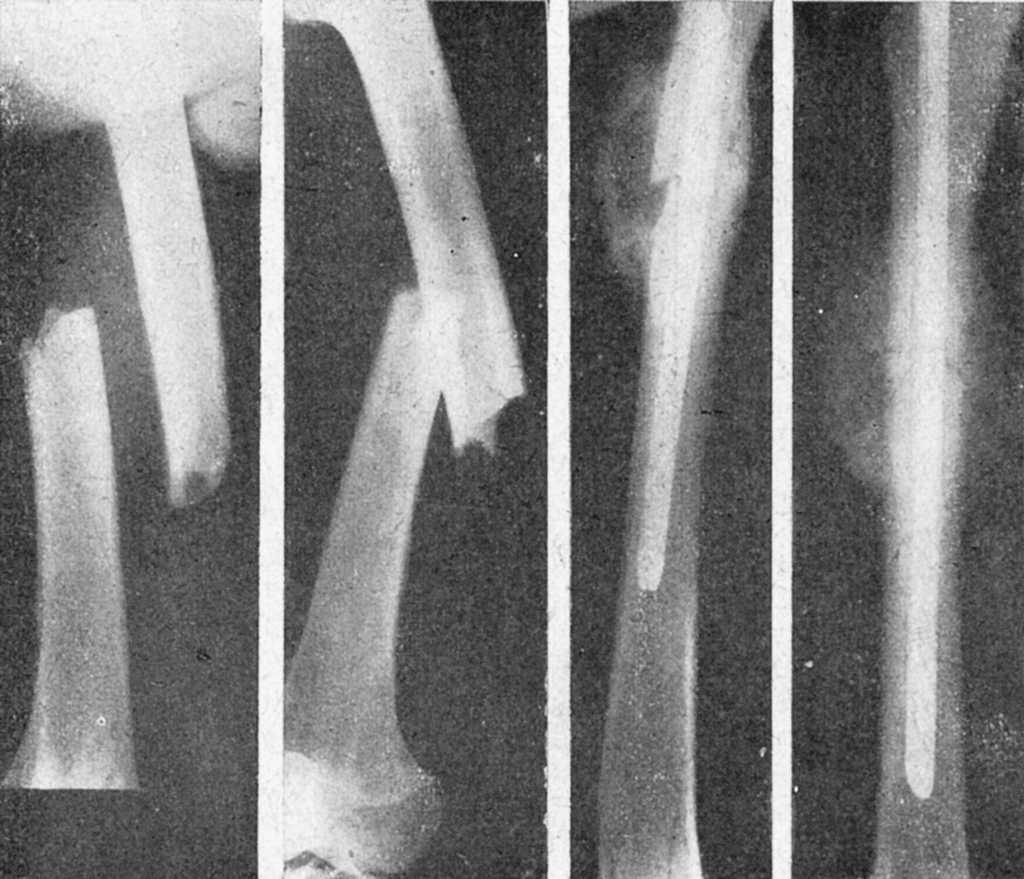

Figura 11. Complicación que se produce por no seleccionar bien el diámetro del clavo; astillamiento del fragmento proximal.

Figura 12. Otra complicación de enclavijamiento cerrado; el fragmento proximal estallado ha sido penetrado por el distal en cuña al impactar; el control radiográfico puso en evidencia el accidente y hubo que retirar el tallo y reducir la penetración; curó sin complicaciones.

Figura 13. Fractura tercio medio fémur con gran desviación fragmentaria, irreducible por interposición muscular, tributaria de la reducción cruenta. La misma, enclavijada y en período de consolidación; callo perióstico exuberante.